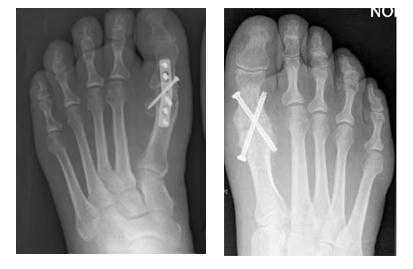

Артродез первого плюсне-фалангового сустава является одновременно и самой крайней мерой и самой распространённой операцией при Hallux Rigidus. Это объясняется тем, что, во-первых, большинство пациентов обращается за специализированной помощью с крайне запущенными случаями, во вторых, артродез эффективно убирает болевую симптоматику в 70-100% случаев. Крайней мерой артродез является по той причине, что после него возвращение к активным занятиям спортом невозможно, по причине изменения биомеханики ходьбы\бега.

Результаты использования наиболее распространённых техник артродеза первого плюсне-фалангового сустава при лечении ригидного первого пальца стопы.

Для операции чаще всего используется тыльная компрессирующая пластина, после удаления суставных поверхностей основная фаланга первого пальца должна фиксироваться в наиболее биомеханически выгодном положении: 10-15° вальгуса и 15° тыльного сгибания. При избыточном сгибании у пациента будут возникать боли в области кончика пальца, в области межфаланговых суставов. При недостаточном тыльном сгибании на большой палец будет приходится избыточное давление. При избыточной вальгусной девиации быстро будет прогрессировать артроз межфаланговых суставов. Однако невзирая на ограничение физической активности, из всех вышеприведённых методов хирургического лечения Hallux Rigidus, артродез является наиболее надёжным способом избавиться от боли и избежать осложнений.